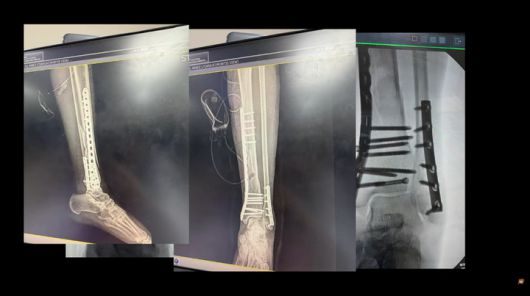

특히 "큰 뼈와 작은 뼈가 모두 부러졌는데, 큰 뼈는 산산조각이 났다"는 그녀의 고백은 부상의 심각성을 짐작게 했다. 이후 2시간여에 걸친 대수술을 받은 엄지원은 병실에서 수술 결과를 확인하며 "미흡한 게 없다"는 의료진의 말에 안도의 눈물을 흘려 보는 이들의 안타까움을 자아냈다.